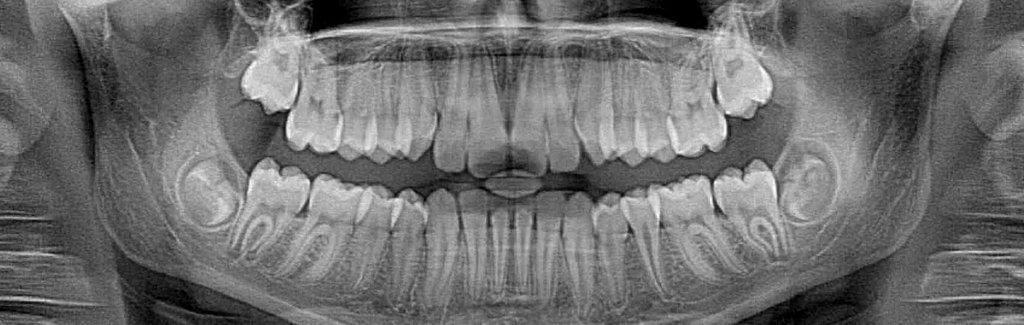

Dental X-rays are essential tools that allow dentists to detect cavities and other issues hidden beneath the surface of teeth that might not be visible during a routine examination. Early detection through X-rays can lead to more effective treatment of dental problems, ultimately benefiting the health of your teeth. While X-rays do involve some radiation exposure, patients are protected by wearing lead aprons during the process. Fortunately, advancements in technology have led to safer imaging methods.

For many years, traditional film X-rays were the standard in dental practices. However, our progressive dentists have transitioned to digital X-ray technology. While film X-rays may be less expensive, they expose patients to significantly higher radiation levels, which can pose health risks. In contrast, our digital X-ray systems emit up to 85% less radiation than conventional methods.

At RR Dentistry, we recognize the tremendous benefits of digital X-rays, having utilized them for nearly two decades. This technology not only reduces radiation exposure but also enhances diagnostic accuracy. Additionally, digital X-rays help us minimize the use of harmful chemicals and waste materials typically associated with traditional X-ray processes, contributing to a healthier environment. Our commitment to reducing environmental impact was a key factor in our decision to adopt this innovative technology, and we take pride in being environmentally conscious. We hope that our efforts inspire others to support and adopt similar eco-friendly practices in their dental care.